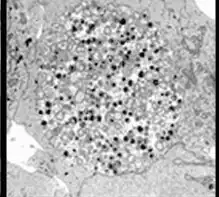

| Chlamydia pneumoniae in HeLa cell 72 hours post infection | |